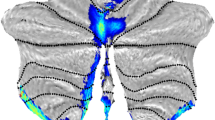

The spinocerebellar ataxias (SCAs) are a genetically heterogeneous group of cerebellar degenerative disorders, characterized by progressive gait unsteadiness, hand incoordination, and dysarthria. The mutational mechanism in SCA1, a dominantly inherited form of SCA, consists of an expanded trinucleotide CAG repeat. In SCA1, there is loss of Purkinje cells, neuronal loss in dentate nucleus, olives, and pontine nuclei. In the present study, we sought to apply intrinsic functional connectivity analysis combined with diffusion tensor imaging to define the state of cerebellar connectivity in SCA1. Our results on the intrinsic functional connectivity in lateral cerebellum and thalamus showed progressive organizational changes in SCA1 noted as a progressive increase in the absolute value of the correlation coefficients. In the lateral cerebellum, the anatomical organization of functional clusters seen as parasagittal bands in controls is lost, changing to a patchy appearance in SCA1. Lastly, only fractional anisotropy in the superior peduncle and changes in functional organization in thalamus showed a linear dependence to duration and severity of disease. The present pilot work represents an initial effort describing connectivity biomarkers of disease progression in SCA1. The functional changes detected with intrinsic functional analysis and diffusion tensor imaging suggest that disease progression can be analyzed as a disconnection syndrome.

Anatomically [21], the lateral cerebellum included the following lobules: V lat (culmen inferior), VI lat (simplex), VIIA_Crus I/1,2 (superior semilunar lobule), VIIA_Crus II/1,2 (inferior semilunar lobule), VIIB lat (paramedian/gracilis), VIIIA lat (biventer, pars copularis), and VIIIB lat (biventer, pars paraflocculus dorsalis).